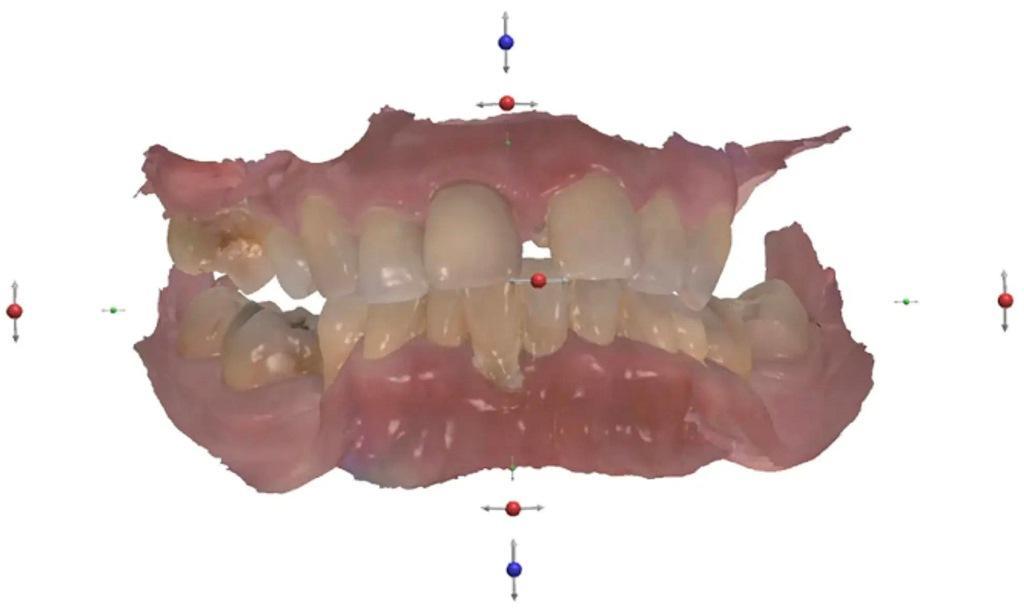

Во время экстраорального обследования никаких отклонений от нормы обнаружено не было. У пациента появилась низкая линия улыбки. При интраоральном осмотре было выявлено нарушение целостности зубного ряда из-за генерализованного пародонтита. Наблюдалась выраженная резорбция заднего отдела верхней челюсти с обеих сторон (фото 1). Рентгенологическое исследование показало резорбцию альвеолярной кости с вертикальными костными дефектами (фото 2).